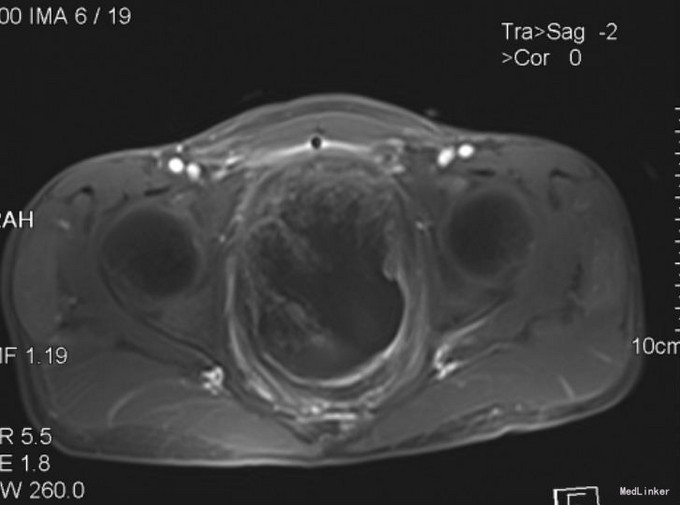

查体:下腹部膨隆,无腹壁静脉曲张,腹式呼吸存在,无胃肠蠕动波,无肠型。腹壁柔软,无压痛、反跳痛,肝脾肋下未及。肝区无叩击痛,脾区无扣击痛,下腹部可触及约12x15cm大小,质韧,边界清楚,活动度欠佳。移动性浊音(-),振水音(-)。肠鸣音5次/分。 2015-9-26 血常规:白细胞 4.9 *10^9/L ,血红蛋白 134 g/L ,血小板 272 X10^9/L 。 生化检验报告:总蛋白 78 g/L ,白蛋白 49 g/L ,谷丙转氨酶 10 U/L ,谷草转氨酶 25 U/L ,碱性磷酸酶 87 U/L ,γ-谷氨酰酶 23 U/L ,总胆红素 6.4 μmol/L ,直接胆红素 3.3 μmol/L ,尿素 2.9 mmol/L ,肌酐 65 μmol/L ,尿酸 238 μmol/L ,胱抑素-C 1.0 mg/L ,血清钾 4.3 mmol/L ,血清钠 140 mmol/L ,血清氯 99 mmol/L ,钙 2.51 mmol/L ,镁 1.02 mmol/L ,磷 1.39 mmol/L 。放免DPC(同位素)检验报告:降钙素原 0.026 ng/mL 。放免DPC(同位素)检验报告:甲胎蛋白(AFP) 1.31 ng/mL ,癌胚抗原(CEA) 1.64 ng/mL ,前列腺特异抗原 0.982 ng/mL ,游离前列腺抗原 0.040 ng/mL ,fPSA/PSA 0.041 ↓,鳞状上皮细胞癌抗原 0.70 ug/L ,糖类抗原(CA125) 15.39 U/mL ,糖类抗原(CA153) 10.43 U/mL ,糖类抗原(CA199) 26.45 U/mL ,神经元特异烯醇化酶 26.18 ug/L ↑,糖类抗原(CA242) 25.24 IU/ml ↑,糖类抗原(CA50) 11.91 IU/ML 。急诊化验检验报告:肌钙蛋白-I 0.165 ↑,CKMB 2.2 ug/L ,肌红蛋白 57.4 ug/L 。2015.9.28正常心电图;胸片:心肺X线未见明显活动性病变。MRI 1.盆腔内巨大肿块影,考虑恶性肿瘤可能,伴出血可能2.膀胱内留置导尿中,盆腔积液。 2015.10.13下腹部CT:腹膜后及盆腔内巨大不规则混杂肿块影,大小约19*9*8cm,肿块向上至髂血管分叉水平,向前延伸至左侧腹股沟区,其内见片状高密度影及积气影,边界欠清,增强后明显不均匀强化,膀胱受压向前上推移,留置导尿中,直肠受压右移,显示欠清,前列腺尚可,未见异常强化灶,盆腔未见明显肿大淋巴结,盆腔积液。

患者入院后完善相关检查,于2015-9-30行盆腔肿块切除术,术后病理:(盆腔):胚胎性横纹肌肉瘤。